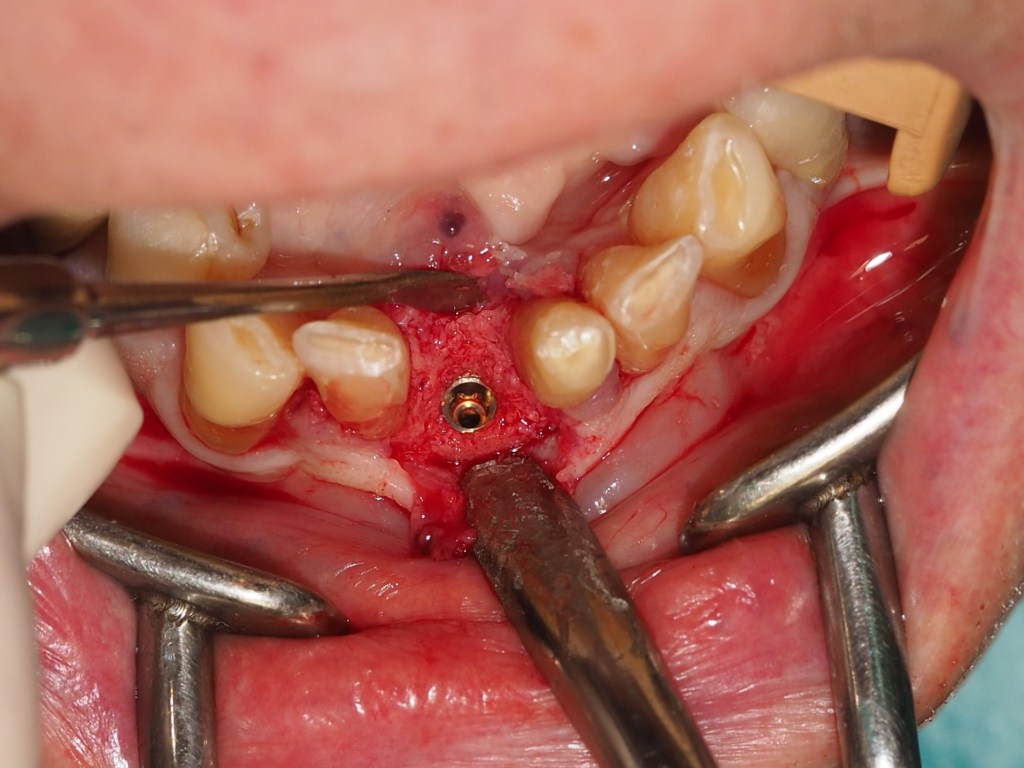

Una vez obtenida una adecuada regeneración ósea (Figuras 13-15), se procede a la colocación de un implante en la posición del 4.1, asegurando una correcta estabilidad primaria (Figuras 16-17).